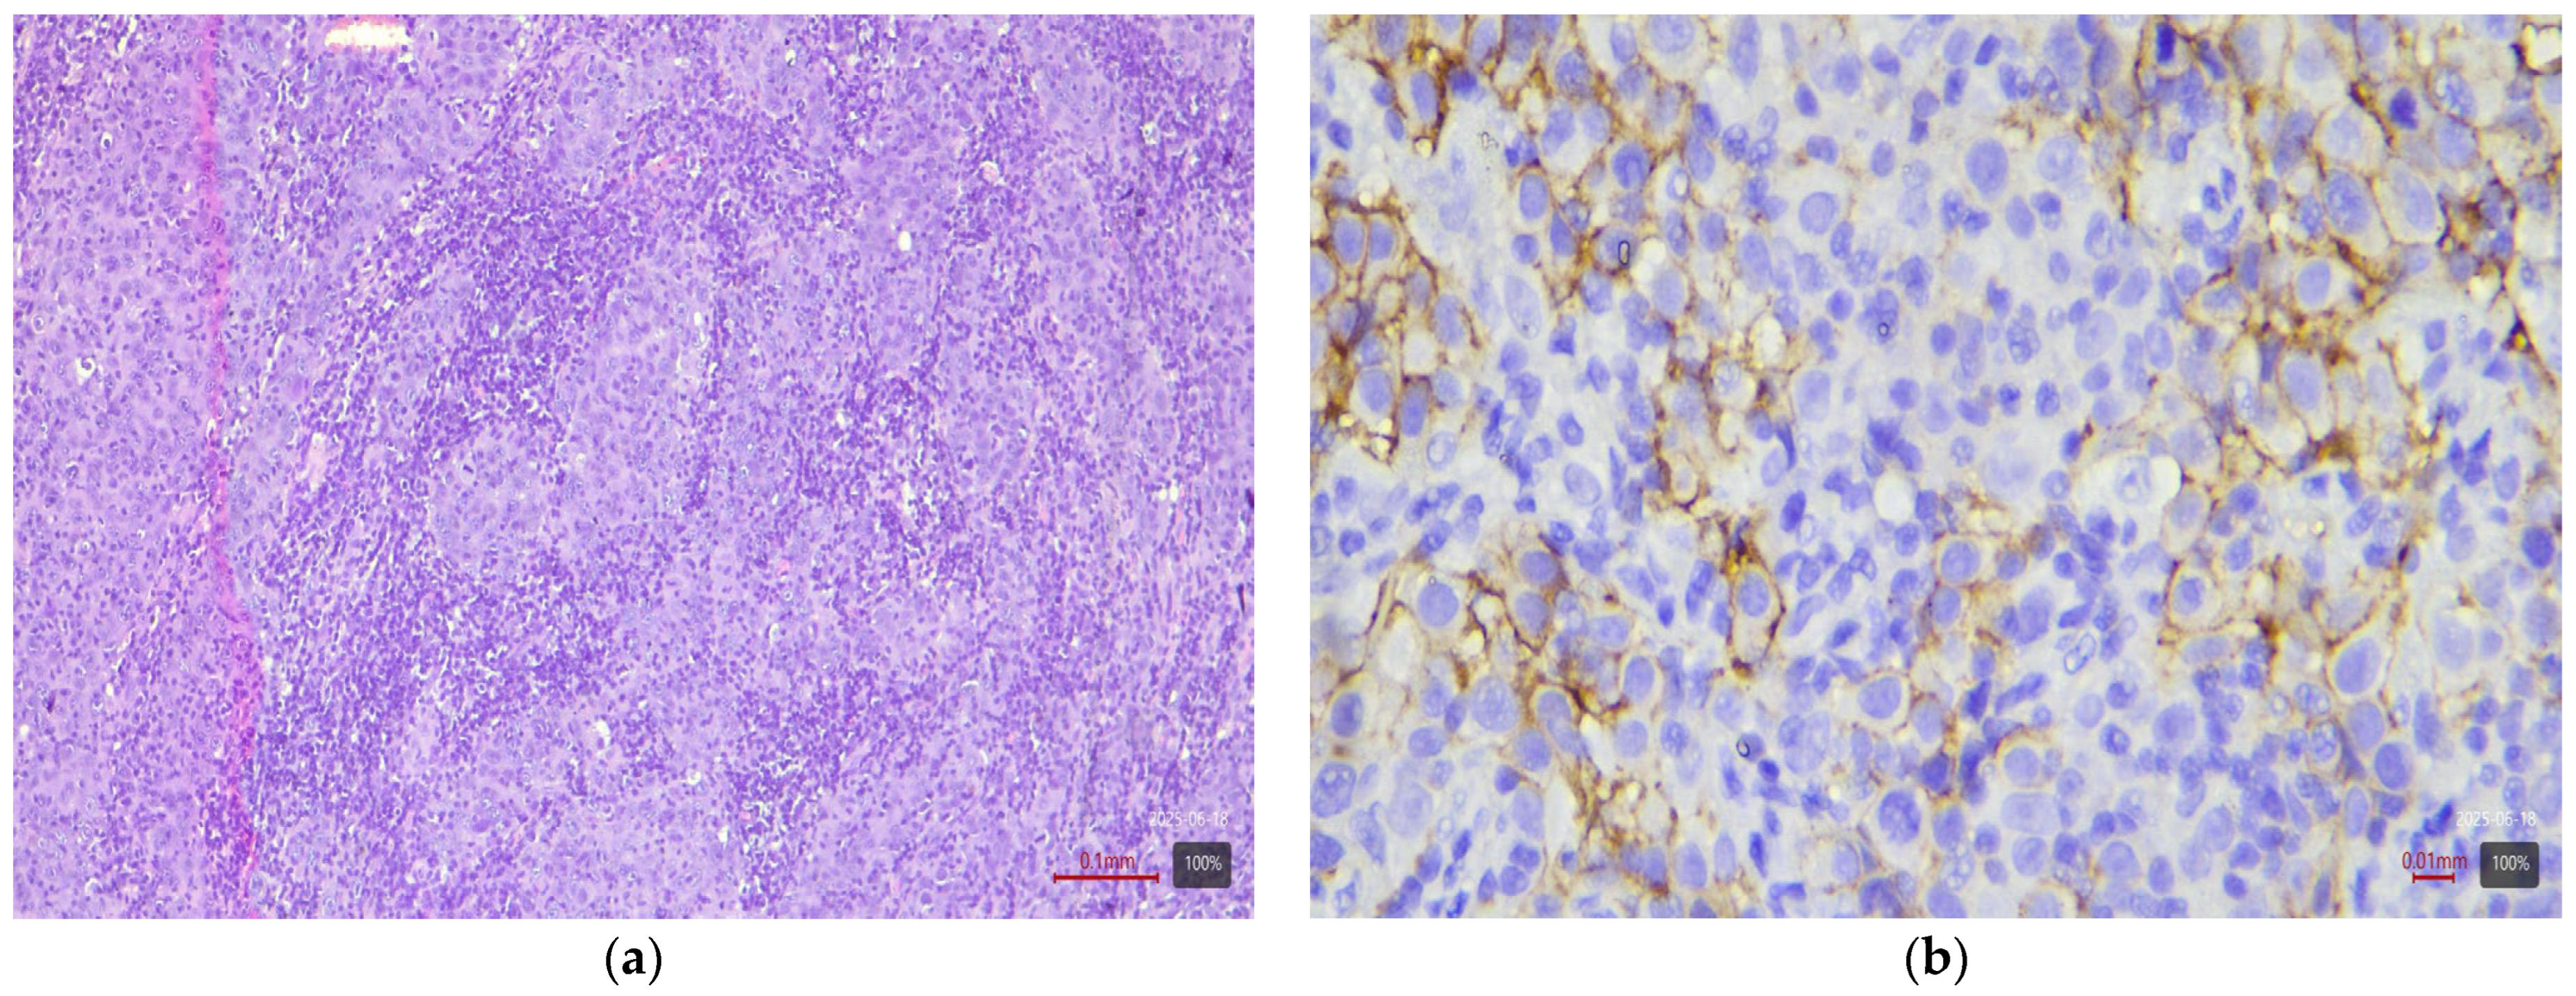

2.3. Histological and Molecular Subtyping of Tumors

2.4. Immunohistochemical Study of HER2

2.5. Interpretation of HER2 Status